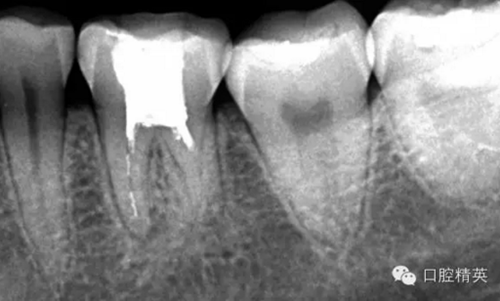

這個(gè)病例是我準(zhǔn)備分根的病例,保留近中根,曾在外院做過干尸長達(dá)數(shù)十年。8號(hào)挫疏通時(shí)近舌根堵,近頰未找到。在這個(gè)病例中首先要知道是為什么根管難以疏通,首先是長時(shí)間的干尸,和患者年紀(jì)較大根管逐漸變窄,根管道路可能會(huì)出現(xiàn)堵塞,在這張病例中我能知道的是稍有不慎就會(huì)形成臺(tái)階,從而導(dǎo)致根管堵塞加重,更加難以疏通。